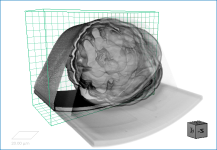

In some cases, you may find it advantageous to apply multiple effects to a visual or visuals. For example, edge contrast and a look-up table.

Multiple effects of edge contrast and a LUT

You should note that when rendering a visual, Dragonfly will apply the selected effects in the order in which they appear in the Effects panel. Reordering effects will have an impact on the final look of the visual by either subtly or dramatically changing its appearance. If required, you can reorder selected effects with the Up and Down buttons on the right side of the panel, as shown below.

Reordering effects